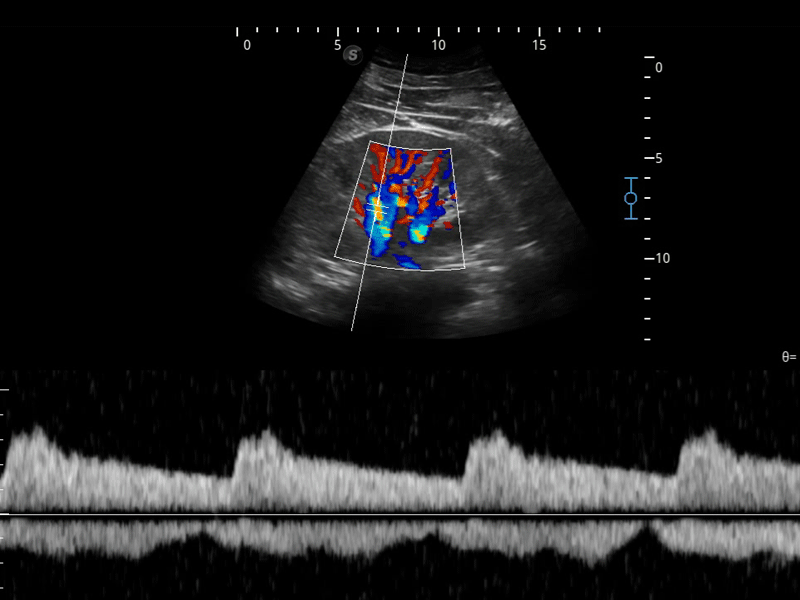

開立醫(yī)療通過不斷的技術(shù)創(chuàng)新,為大眾的生命健康提供持續(xù)關(guān)愛。P12 Plus采用全新一代超聲成像平臺,新平臺旨在將真實(shí)還原組織解剖結(jié)構(gòu)作為首要目標(biāo)。平臺采用全新集成化硬件模塊,搭載新一代芯片,系統(tǒng)性能得到大幅提升,為您的診斷提供了豐富的臨床信息。優(yōu)異的圖像表現(xiàn),豐富的探頭配置,全面的應(yīng)用功能,為您日常診斷提供了可靠的助手。

彩色多普勒超聲診斷系統(tǒng)